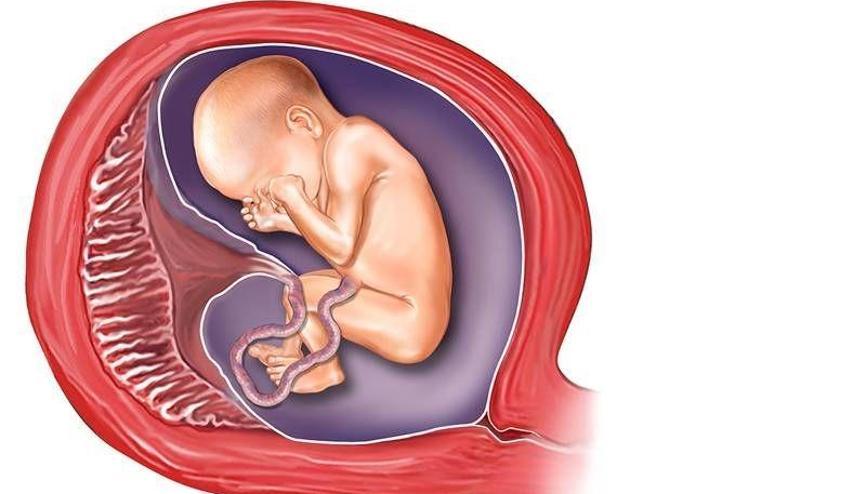

Околоплодный пузырь и плацента: структура и функции